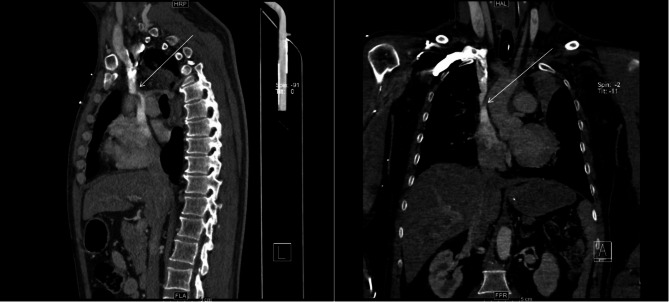

Case presentation: We report the first case of SVC syndrome in an adult patient with pre-existing SVC angulation, exacerbated by cannula placement during VV ECMO therapy. Serial venous-phase chest CT scans (pre-ECMO and during ECMO support) demonstrated progressive luminal narrowing at the cannula tip site, correlating with clinical manifestations of SVC obstruction. The patient was successfully weaned from VV ECMO, achieved complete resolution of SVC syndrome symptoms, and was discharged without neurological sequelae.

Conclusions: This case provides definitive imaging evidence that ECMO cannula placement alone can induce acute SVC stenosis in patients with pre-existing vascular tortuosity. Our findings strongly advocate for pre-procedural vascular imaging assessment and real-time monitoring during ECMO support to mitigate this life-threatening complication.